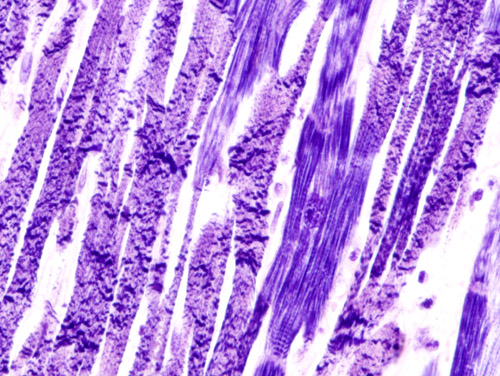

back acute myocardial infarction

Source: Acute_myocardial_infarction_with_contraction_band_necrosis_(1)_PTAH.JPG